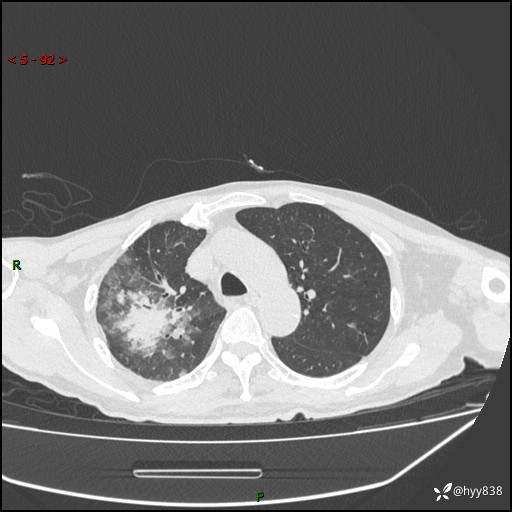

一个月后第二次CT检查(常规抗感染,患者不配合:增强、住院---)